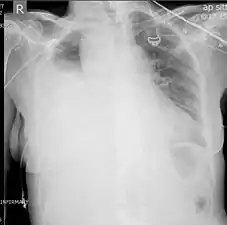

![]() صورةٌ صدرية بالأشعة السينية تُظهر تدَمّي الصدر في الجانب الأيسر (السهم) صورةٌ صدرية بالأشعة السينية تُظهر تدَمّي الصدر في الجانب الأيسر (السهم) | |

تصوير الصدر بالأشعة السينية

يُعتبر تصوير الصدر بالأشعة السينية أكثر تقنياتِ التصوير استعمالًا في تشخيص تدمي الصدر.[8] يجب أن يُجرى التصوير بالأشعة السينية في وضعٍ مُستقيم (يكون الشخص قائمًا)، ولكن إذا كان هذا غير ممكنٍ فيُمكن إجراؤه في وضعية الاستلقاء على الظهر. أثناء إجراء تصوير الصدر بالأشعة السينية في وضعيةٍ مُستقيمة، فإنهُ يُتوقع وجود تدمي الصدر إذا كان الردب الضلعي الحجابي غيرُ واضحٍ أو مُعتمًا جزئيًا أو كليًا في النصف المُصاب من الصدر. أما في وضعية الاستلقاء، فإنَّ الدم يُشكل طبقةً في التجويف الجنبي، وبالتالي يُمكن توقع حدوث تدمي الصدر عبر مقارنةِ الجانب المُصاب بالجانب السليم، فيكون الجانب المُصاب أقل وضوحًا (ضبابيًا).

قد لا يُشخص تدمي الصدر الصغير عبر تصوير الصدر بالأشعة السينية؛ وذلك لأنَّ عدة مئاتٍ من ملليلترات الدم قد لا تظهر بسبب اختفائها في الحجاب الحاجز وأحشاء البطن أثناء التصوير بالوضعية المُستقيمة، أما في وضعية الاستلقاء فإنها تكون أقل حساسيةٍ بحيث قد لا يظهر لترٌ واحدٌ من الدم وبالتالي لا يتم التشخيص.[20]

تصوير صدري بالأشعة السينية يُظهر تدمي صدري كبير في الجانب الأيمن